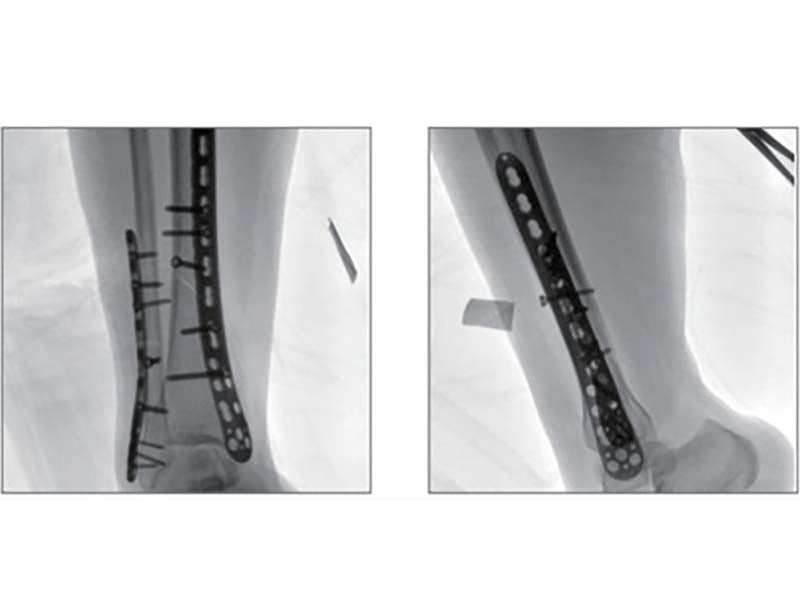

Compared to the conventional 9” image intensifier, a 9” x 9” flat panel detector is able to expand the FoV by 22%, providing more perspective for clinical diagnosis.

Higher signal coversion efficiency of FPD ensures higher image quality and lower dose.

16 bits depth determines maximum 65536 greyscale value, providing HD resolution for revealing more anatomical details.